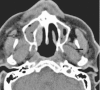

We present a case of rhino-orbitary mucormycosis which progressed despite liposomal amphotericin and early surgical debridement. Combined echinocandin and high dose liposomal amphotericin, repeated debridement, prolonged therapy with hyperbaric oxygen and continued therapy with posaconazole, along with strict diabetic control, allowed cure without disfigurement.